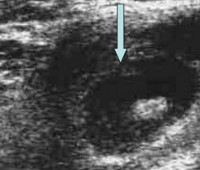

УЗИ лимфатических узлов. Исследование лимфатических узлов ультразвуком. Используется на этапе диагностики, дифференциальной диагностики первичных онкологических поражений лимфоидной системы, лимфатических метастазов опухолей других органов и систем, лимфаденопатии при специфических и неспецифических инфекциях. Это позволяет определять диаметр, форму, положение, структуру отдельных лимфатических узлов, идентифицировать упаковки и конгломераты, а также оценивать вовлечение окружающих тканей при наличии аденопатии. Как правило, в клинической практике УЗИ проводится на лимфатических узлах 1 или 2 группы. Исследование абсолютно безопасно, оно не требует подготовки.

Размер неизмененных лимфатических узлов обычно не превышает 0,8-1 соотношение длины и толщины - не более 1: 2. Контуры ровные, четкие, структура равномерно эхогенная. Повреждение лимфатических узлов может сопровождаться изменением формы, расширением, неодинаковыми контурами, структурной неоднородностью, образованием пакетов или образованием конгломератов. Врач ультразвуковой диагностики описывает все обнаруженные изменения в заключении и отправляет документ пациенту или лечащему врачу. Степень создается в течение нескольких часов или дней в зависимости от загруженности специалиста.